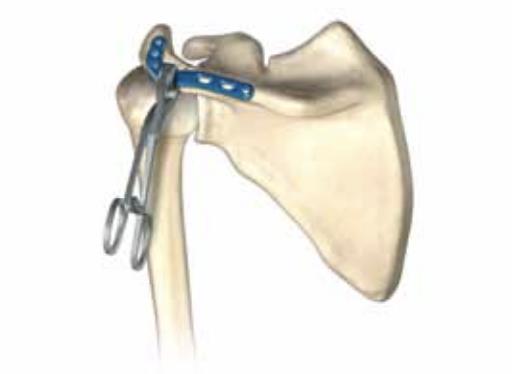

• Acromion Plate

• Provides fixation for fractures along the acromion of the scapula spine

• Designed to closely match the patient's natural acromion curvatures, which may help in the reconstruction of even severely displaced acromion fractures

• An integral piece of the Scapula Plating System, and may be used individually or together with the Acumed Medial Border Plate, Lateral Border Plate, and Glenoid Plate

• The plate is placed on the superior surface to stabilize the fractures of the acromion and/or scapula spine

• In the case of a non-union or malunion the curve of the plate can assist in the anatomic reduction of the acromion